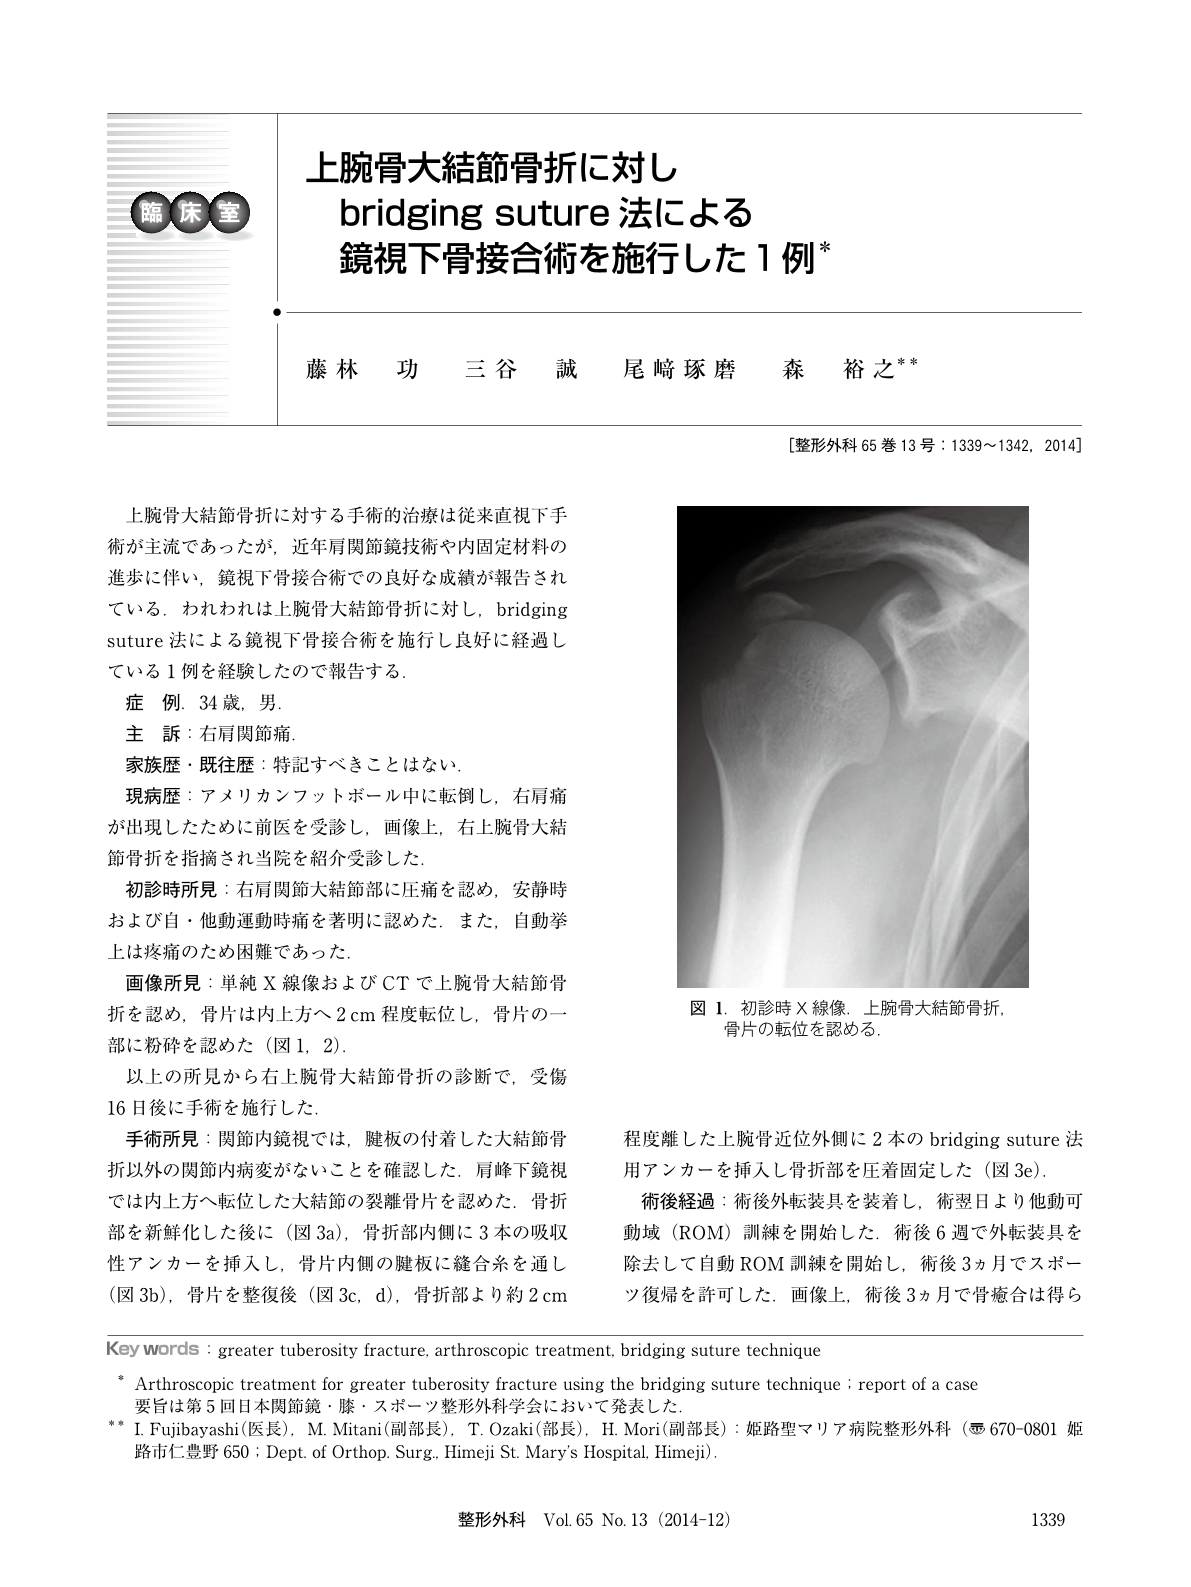

上腕骨大結節骨折に対しbridging Suture法による鏡視下骨接合術を施行した1例 臨床雑誌整形外科 65巻13号 医書 Jp

大結節骨折の手術とリハビリテーションを専門医が徹底解説

大結節骨折の手術とリハビリテーションを専門医が徹底解説

大結節骨折の手術とリハビリテーションを専門医が徹底解説

大結節骨折の手術とリハビリテーションを専門医が徹底解説

大結節骨折の手術とリハビリテーションを専門医が徹底解説

大結節骨折の手術とリハビリテーションを専門医が徹底解説

大結節骨折の手術とリハビリテーションを専門医が徹底解説